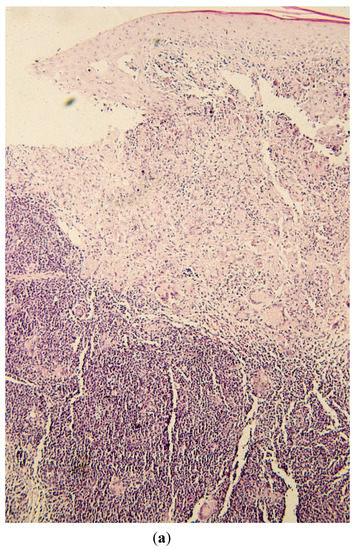

(a) Biopsy demonstrating both leukemic infiltrate and granuloma formation within the dermis, the latter being located more superficially (hematoxylin-eosin stain at 50×); (b) closer view of the biopsy demonstrating both leukemic infiltrate and granuloma formation with prominent multinucleated giant cells (Hematoxylin-eosin stain at 125×).

Histopathologic examination in hematoxylin and eosin (H&E)-stained sections revealed concurrent and adjacent leukemic infiltrate consisting of mature lymphocytes and granulomata with obvious giant cells (Figure 2a,b).